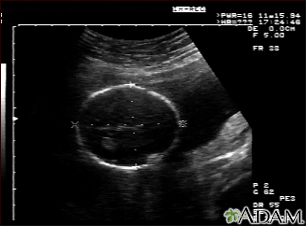

Ultrasound, normal fetus - head measurements